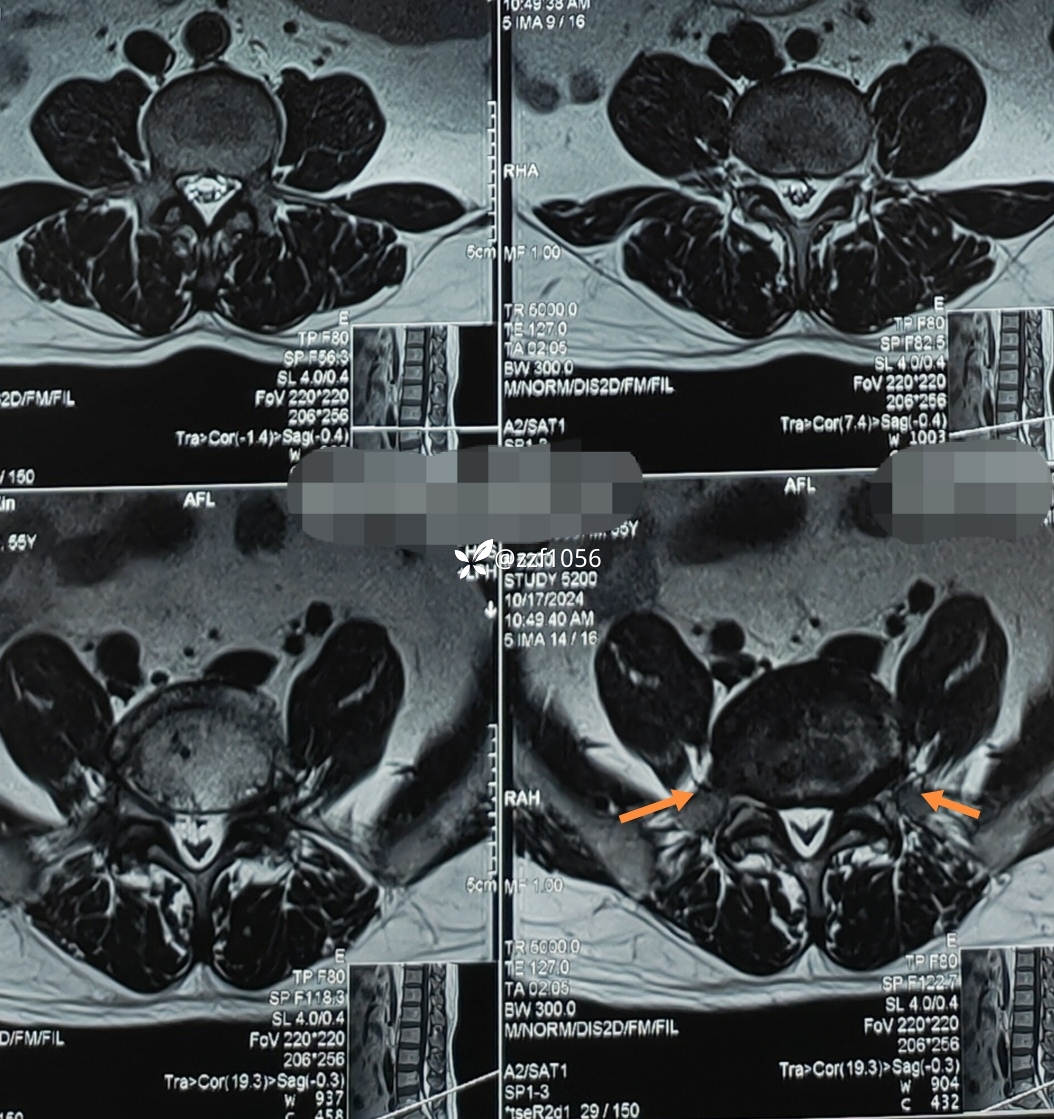

极外侧突出吗

影像上可看到L5/S1间隙非常狭窄,退变严重,两侧均有神经根激惹,椎间孔狭窄,L5下终板终板炎较重,左下肢无任何症状,右下肢L5S1根症状均存在,建议椎间孔镜下减压L5根和S1根,患者拒绝,因咨询多家医院要求开放融合。